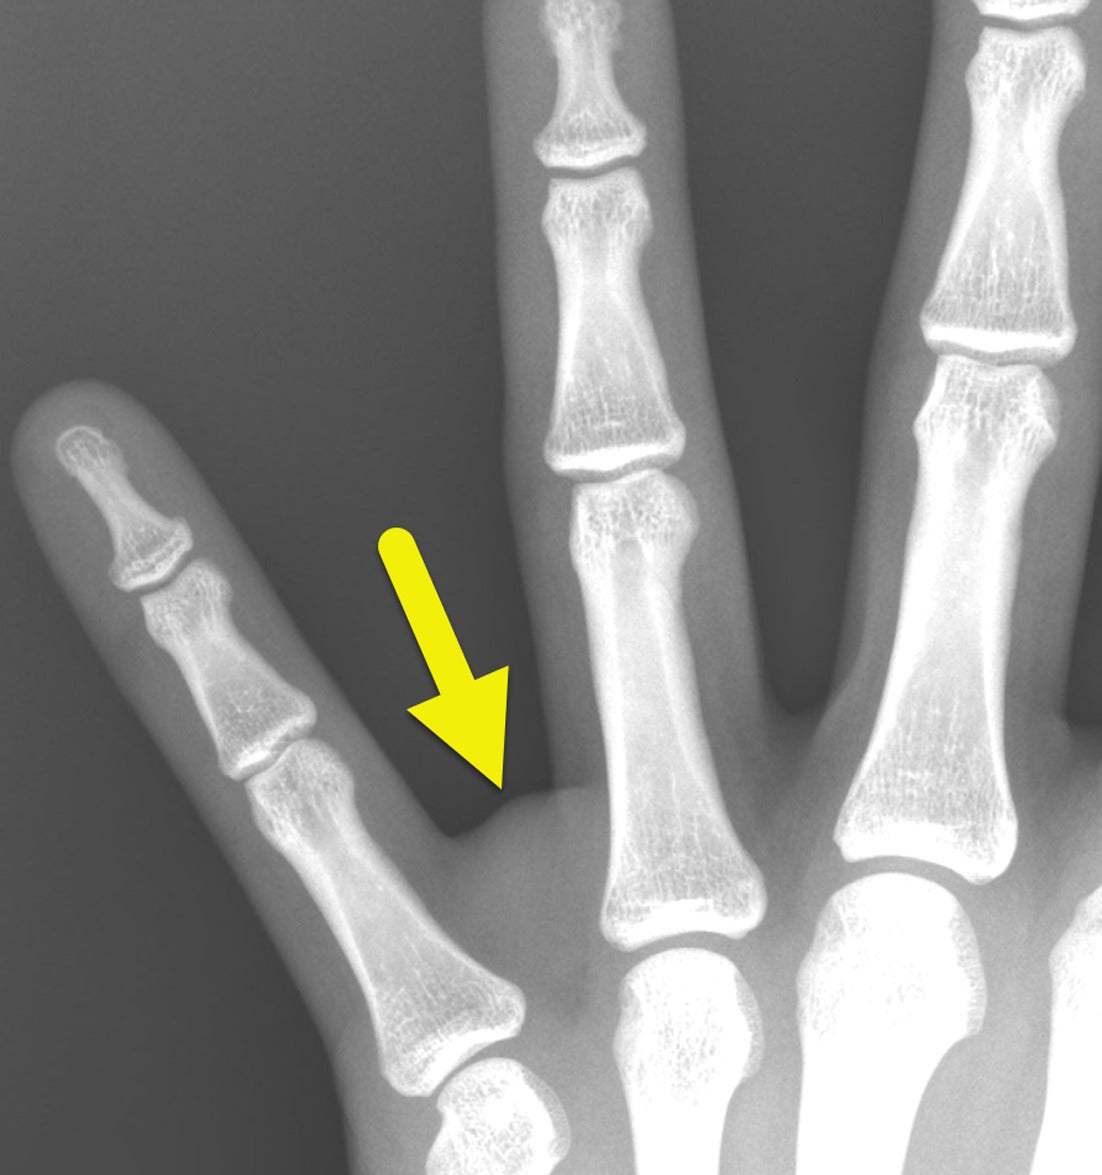

A radiograph of the left hand ( Figure 1 ) revealed a soft tissue mass in the web space between the ring and small fingers. No osseous abnormalities were noted. Ultrasound (US) ( Figure 2 ) demonstrated a well-circumscribed, hypoechoic soft tissue mass measuring 1.4×1.3×1.6 cm. No internal vascularity was noted.

Magnified radiograph of the hand shows a soft tissue mass (arrow) in the web space between the ring and small fingers. A small amount of relatively lucent fat is present on the more proximal aspect of the tumor.

Radiographically, LGFMS appears as a noncalcified soft-tissue mass without adjacent bone erosion or destruction ( Figure 1 ).4 It is a solid hypoechoic mass on US with a more hypoechoic rim.4 It may have regions of nodularity and minimal internal blood flow on color Doppler ( Figure 2 ).4 The tumor is heterogeneous on CT, with heterogeneous enhancement and hypodense relative to muscle.4, 5 On MRI, the mass is hypo- to isointense compared with muscle on T1-weighted images and heterogeneous on T2-weighted images.5 It enhances heterogeneously after the administration of contrast media. Peritumoral edema is common.5 When an LGFMS is located within an intramuscular compartment, the “split fat” sign may be present.5 This finding is present when a rim of fat surrounds the tumor. The tumor may also have a gyriform pattern on T2-weighted or post-contrast sequences.4